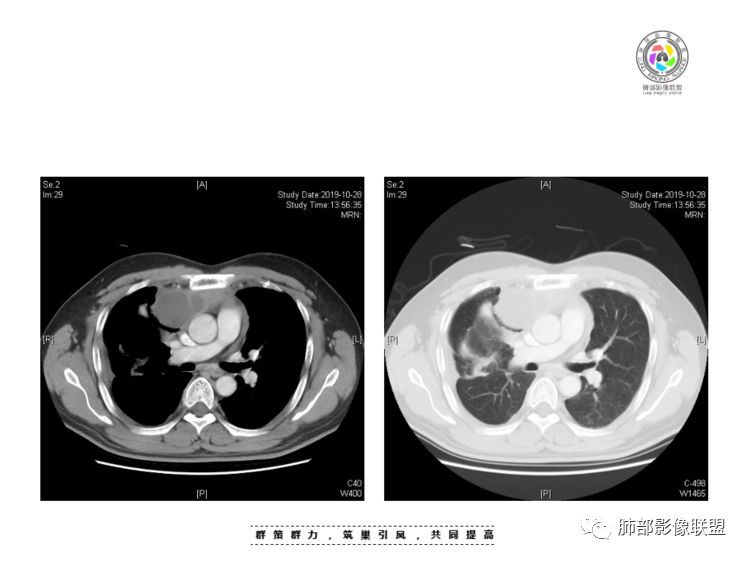

南边:我总觉得这个纵隔内不像是一个肿块的改变,扁平,周围蔓延:有符合炎性的的特点,或者肿瘤的侵犯;但是肿瘤的侵犯,不大符合,实性部位的边缘过于柔和,没有毛糙的侵犯边缘。

如果前纵隔淋巴瘤,囊在中央,周围大量实性才对

2、前纵隔内病灶囊实性混杂密度病灶,囊性病灶主要位于右侧,张力较高,有分隔影,囊壁右侧缘光整,病灶左侧实性部分边界不清明显强化,病灶肺瘤交界面大部分边界清楚,部分模糊。

前纵隔肿块伴囊变坏死常见以有胸腺瘤、胸腺癌、淋巴瘤和生殖细胞肿瘤。

纵隔内病灶不符合肺癌转移途径,且纵隔内单发的囊实性转移罕见。淋巴瘤无论是分布、形态、密度、还是强化方式度不符合。

胸腺瘤/胸腺癌:病灶内那么大的囊,常规考虑B型以上胸腺瘤,囊内有分隔影,病灶周围脂肪间隙模糊,常规考虑侵袭性胸腺瘤或胸腺癌,若侵袭性胸腺瘤,常侵犯胸膜、心包,很少累及肺。胸腺癌易侵犯胸膜、肺并纵隔淋巴结及远处转移。但肺内腺癌形态更符合原发灶。胸膜及叶间裂转移则即可来自肺,也可来自胸腺癌。